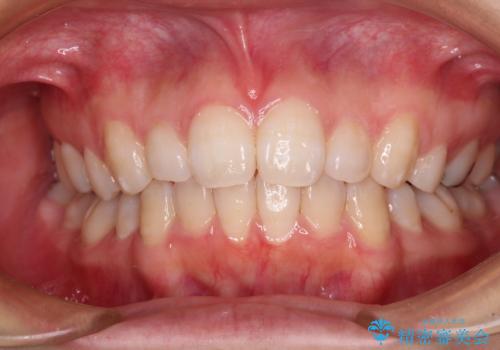

- 下顎前歯を中心に、以前行った矯正治療の後戻りが気になるとのことで来院された患者様です。

後戻りは軽度であったため、インビザライン・ライトにて治療を行うこととしました。

治療途中で出産をされたため、通院が困難となりましたが、インビザライン・ライトでの治療可能期限である2年以内に無事に治療を終えることができました。